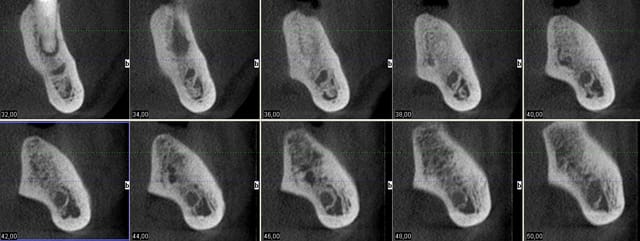

Et voilà l'objet du délit

3dslice1 2011 05 17 20 03 31 ohbadz - Eugenol

bein aux vues de tes images...si, tu as du taper la corticale linguale...

Je pense aussi que l'apex des implants est dans la corticale linguale

dudule, seul un cliché 3D te dira ce qu'il c'est vraiment passé...mais le coup de la corticale, c'est un classique...et plus que plausible ici...

regardes à nouveau tes images de planification...déjà à ce niveau l'axe de tes implants part légèrement en lingual...avec un apex bien amarré dans la dite corticale linguale...

il suffit que tu pointes avec ton premier foret un poil plus lingual encore pour amplifier le problème...

pour moi, à 99%, c'est à cause de la corticale que t'as pas pu aller plus loin...